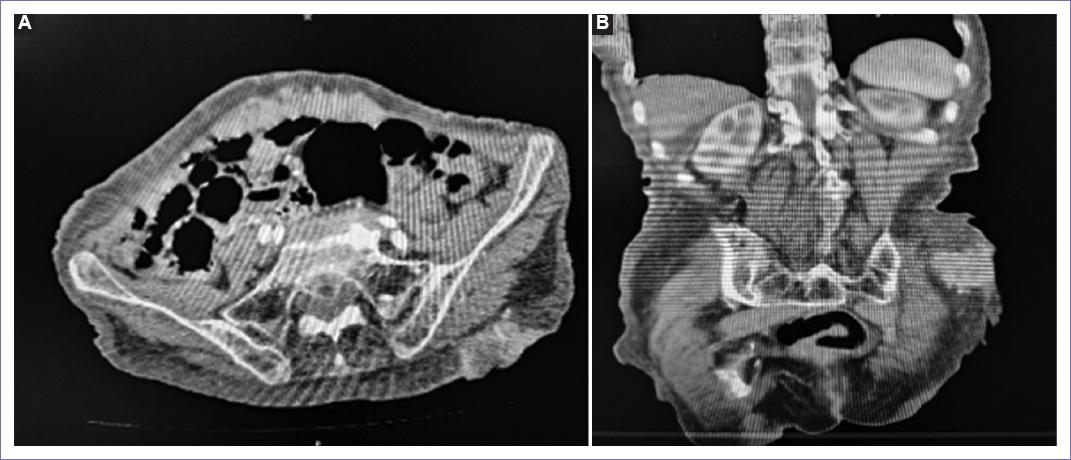

Se realizaron estudios de gabinete, como tomografía de abdomen (Fig. 2), donde se reporta lesión ocupante en región glútea izquierda con afectación de piel y tejido celular subcutáneo sin afectar hasta plano fascial.

Figura 2 A: tomografía axial de abdomen en fase contrastada con presencia de tumor en glúteo izquierdo. B: imágenes coronales por tomografía abdominal contrastada donde se evidencia tumor en glúteo izquierdo hasta fascia muscular.